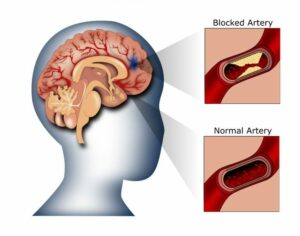

(1) Đột quỵ nhồi máu não (ischemic stroke):

Loại này phổ biến hơn, xảy ra khi một cục máu đông chặn dòng chảy của máu đến một phần của não. Nó có thể liên kết với các bệnh lý như fibrillation atrial (rung nhĩ), bệnh động mạch vành, hoặc xơ vữa động mạch.